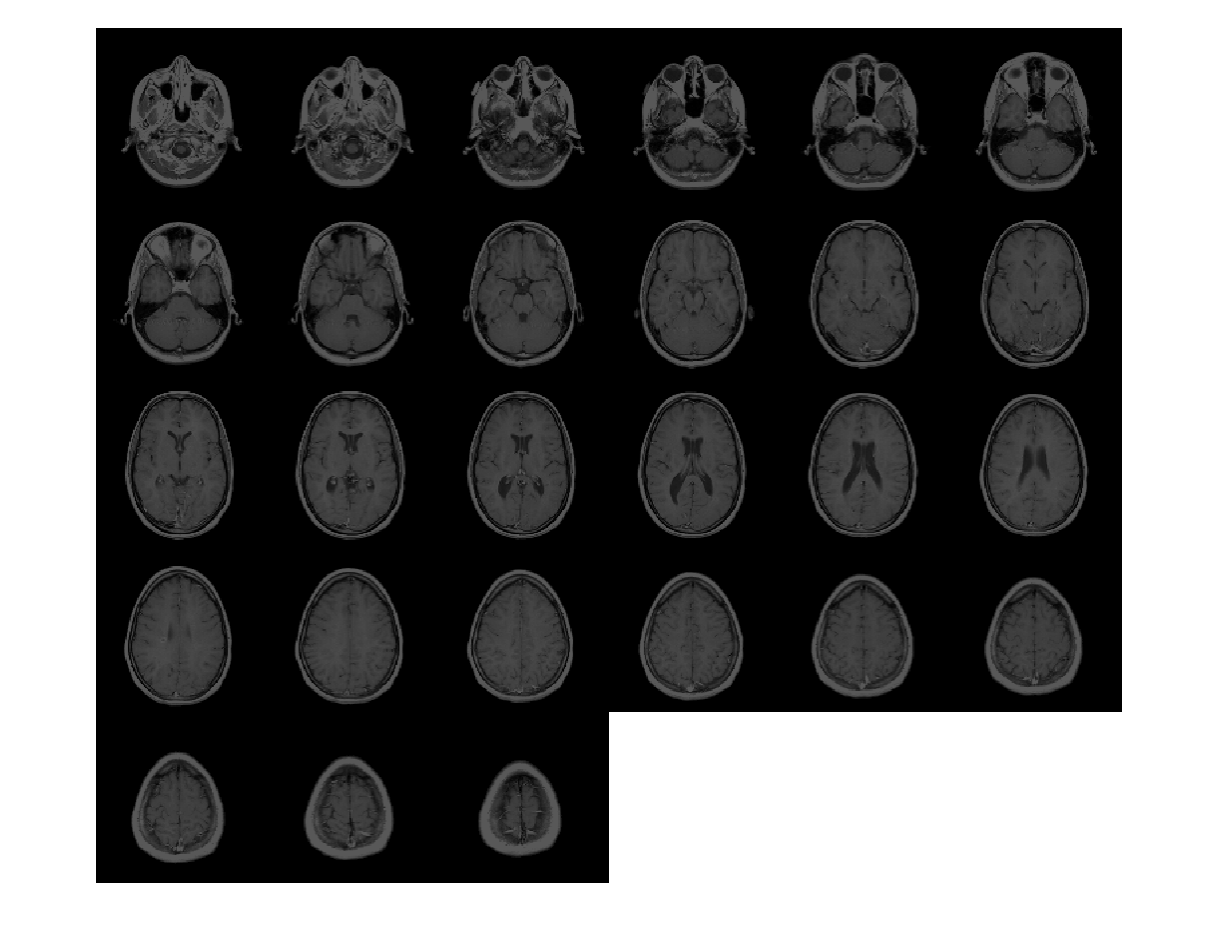

Загрузите 3-D полутоновый объем MRI. Отобразите плоскости объема.

load mristack;

montage(mristack,'BackgroundColor','w')

Figure contains an axes. The axes contains an object of type image.